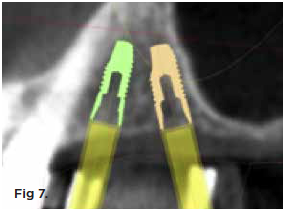

Fig 7. Tilted implant solutions for maxillary posterior partial edentulism. In the same manner that tilted implants can be used to

avoid the need for sinus grafting in full-arch implant prostheses, they can be used to avoid direct or indirect sinus grafting when insufficient posterior

maxillary bone volume challenges a fixed dental prosthesis implant restoration. Fig 7: Software planning for implant placement is shown with

tilting of the distal implant along the anterior wall of the maxillary sinus where there is insufficient bone in zone 3. Fig 8: Postoperative radiograph

of the implants and abutments reveals the angulation of the implant resolved by the CAD/CAM abutment. Fig 9: Final radiograph of the implant

prosthesis following restorations demonstrates the inclusion of a tooth in the molar position without sinus grafting.

Figure 7